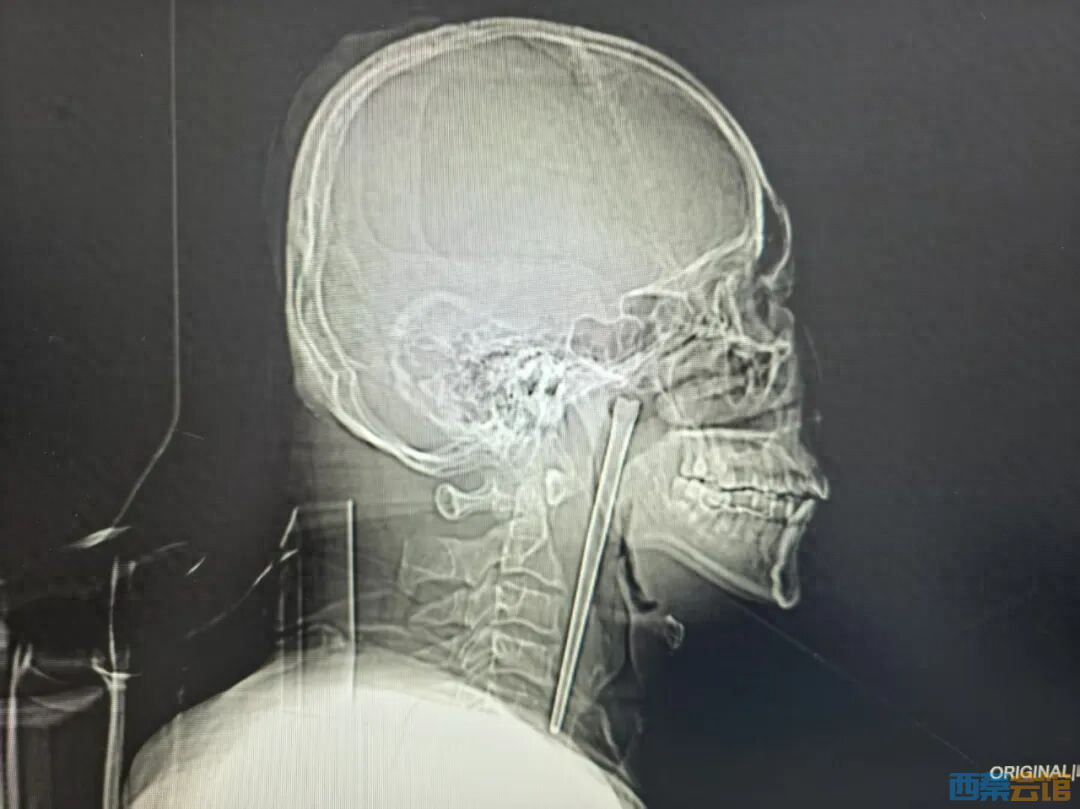

近日,大连理工大学附属中心医院耳鼻咽喉头颈外科收治了一名特殊患者。今年46岁的王先生因咽部突发剧烈疼痛、异物感强烈而紧急就医,影像检查的结果让医护人员都感到意外——一根长达12厘米的金属筷子,竟然已经在他咽部“滞留”了整整八年。

经详细检查发现,一根金属筷子嵌顿于王先生右侧咽后壁上方、软腭后侧,体外可见部分长约3厘米。值得庆幸的是,筷子周围的咽部黏膜并未出现明显破损、出血或化脓,声带活动及喉腔结构也未受压迫。

考虑到患者曾因顾虑传统颈部切开手术而放弃治疗,耳鼻咽喉头颈外科团队为他量身定制了经口腔入路的微创手术方案。手术无需在颈部切口,最终顺利将整根长达12厘米的不锈钢筷子完整取出。术中出血极少,未出现任何并发症,患者术后恢复良好,终于摆脱了长达八年的“心头之患”。